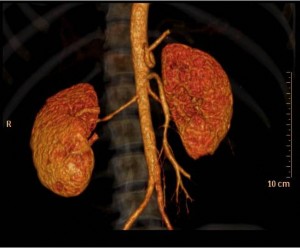

- CT angiography – Computerized tomography angiography (i.e. CTA) is increasingly being used to scan for fibromuscular dysplasia. Surprisingly, this technique is still not well validated, although better imaging techniques and reconstruction programs offer very good views of the renal arteries:

-